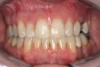

Figure 6f  Jackscrews were activated 0.5 mm/day after 5-day latency period. Note pure translation of segments without tipping. Result 8 months postsurgery. Tooth No. 12 was converted to a canine, and an implant was placed in regenerate bone. Note amount of alveoloskeletal correction and increase in volume of maxillary arch. Also note in Figure 6c and Figure 6c the amount of protraction of maxillary anterior segments while anchorage was maintained in posterior segment. Restorative dentist: Michael E. Carter, DDS.

Figure 6f

Figure 6g  Jackscrews were activated 0.5 mm/day after 5-day latency period. Note pure translation of segments without tipping. Result 8 months postsurgery. Tooth No. 12 was converted to a canine, and an implant was placed in regenerate bone. Note amount of alveoloskeletal correction and increase in volume of maxillary arch. Also note in Figure 6c and Figure 6c the amount of protraction of maxillary anterior segments while anchorage was maintained in posterior segment. Restorative dentist: Michael E. Carter, DDS.

Figure 6g

Figure 6h  Jackscrews were activated 0.5 mm/day after 5-day latency period. Note pure translation of segments without tipping. Result 8 months postsurgery. Tooth No. 12 was converted to a canine, and an implant was placed in regenerate bone. Note amount of alveoloskeletal correction and increase in volume of maxillary arch. Also note in Figure 6c and Figure 6c the amount of protraction of maxillary anterior segments while anchorage was maintained in posterior segment. Restorative dentist: Michael E. Carter, DDS.

Figure 6h

Figure 6i  Jackscrews were activated 0.5 mm/day after 5-day latency period. Note pure translation of segments without tipping. Result 8 months postsurgery. Tooth No. 12 was converted to a canine, and an implant was placed in regenerate bone. Note amount of alveoloskeletal correction and increase in volume of maxillary arch. Also note in Figure 6c and Figure 6c the amount of protraction of maxillary anterior segments while anchorage was maintained in posterior segment. Restorative dentist: Michael E. Carter, DDS.

Figure 6i